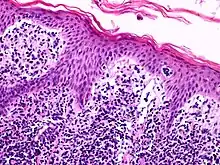

Lutzner cells were discovered by Marvin A. Lutzner, Lucien-Marie Pautrier, and Albert Sézary. These cells are described as the smaller forms of Sézary cells, or Sézary-Lutzner[1] cells, and the two variants are recognised as being morphologically different. Aggregates of these cells in mycosis fungoides are known as a Pautrier's microabscesses. They are a form of T-lymphocytes that has been mutated[2] This atypical form of T-lymphocytes contains T-cell receptors on the surface and is found in both the dermis and epidermis layers of the skin. Since Lutzner cells are a mutated form of T-lymphocytes, they develop in bone marrow and are transported to the thymus is order to mature.[3] The production and maturation stages occur before the cell has developed a mutation. Lutzner cells can form cutaneous T-cell lymphoma, which is a form of skin cancer.[4]

Lutzner cells begin developing in bone marrow then travel to the thymus via the secretion of the hormone thymosin. The secretion allows them to differentiate and mature. Once the mutated cell is developed, it patiently waits in the thymus until an antigen presents itself.[3] When a cutaneous lymphocyte antigen is expressed in the skin, the CD4+ Lutzner cell travels to the epidermis and dermis layers of the skin in order to bind to the antigen.[5]

It is the most common type and diverse range of lymphoma. Normally, it occurs with a B cell becoming abnormal, but also occurs when a T cell becomes abnormal. The mutated cell then divides to create multiple cells. Lymphoma cells can be distributed all over the body and into various tissues.[10] Lutzner cells are found in skin tissue, more specifically, the epidermis and dermis layers. An accumulation of Lutzner cells in the layers of the skin can cause cutaneous T-cell lymphoma. Cutaneous cell lymphoma is the second most common form of non-Hodgkin's lymphoma.[11] Two forms of cutaneous T-cell lymphoma associated with abnormal T-lymphocytes or Lutzner cells are Mycosis Fungoides and Sézary Syndrome.[12] These two diseases are very similar, but both present themselves in different ways.